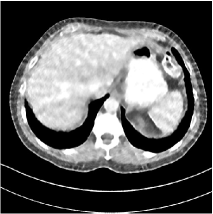

Refer to caption WavResNet [11]Refer to caption WavResNet [11]Refer to caption WavResNet [11]Refer to caption Momentum-Net (SimpleCNN)Refer to caption Momentum-Net (SimpleCNN)Refer to caption Momentum-Net (SimpleCNN)Refer to caption Momentum-Net (SimpleCNN-RSN)Refer to caption Momentum-Net (SimpleCNN-RSN)Refer to caption Momentum-Net (SimpleCNN-RSN)Refer to caption Momentum-Net (Dn-RSN)Refer to caption Momentum-Net (Dn-RSN)Refer to caption Momentum-Net (Dn-RSN)Refer to caption ReferenceRefer to caption ReferenceRefer to caption Reference

Refer to caption Refer to caption Refer to caption Refer to caption Refer to caption Refer to caption Refer to caption Refer to caption Refer to caption Refer to caption Refer to caption Refer to caption Refer to caption Refer to caption Refer to caption

Fig. 3: Three examples (from top to bottom) of the reconstructed testing images using Momentum-Net with SimpleCNN (the second column), with SimpleCNN-RSN (the third column), and with Dn-RSN (the fourth column). The compared WavResNet denoised images are shown in the first column, and the reference images are in the fifth column. See their FBP images in Fig. 4.

Fig. 2 shows that the proposed Momentum-Net with SimpleCNN decreases RMSE dramatically in the first 30 layers, and tends to converge in 50 layers. The Momentum-Net reduces the mean RMSE value by 4.5 HU and gives smaller standard deviations in RMSE, compared to WavResNet, as reported in Table 1. This implies that the proposed Momentum-Net with SimpleCNN can improve both the accuracy and stability of low-dose CT image reconstruction than a state-of-the-art image denoising deep NN, WavResNet. The proposed Momentum-Net with SimpleCNN better removes noise and streak artifacts than WavResNet. It also provides clearer reconstructions of some details; see, in Fig. 3, the boundaries shown in the zoomed region at the top-right corner in the first example, the arrow pointed structures in zoomed areas of the second example, and the arrow pointed tissues in the left zoomed region in the third example.

3.3 Momentum-Nets involving RSN-based training